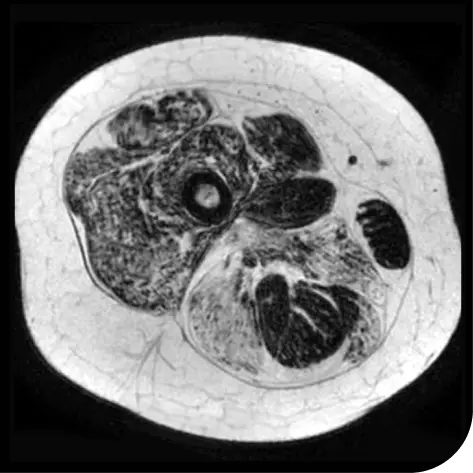

In another follow-up analysis of the clinical trial (meaning it was not one of the main measures planned when the study began), researchers looked at individual people to see how much new fat was in the muscle. The images below represent results from 2 individual people from the study after 18 months. These results may not be the same for everyone.

How to read these images:

- Magnetic resonance spectroscopy (MRS) images can show the difference between muscle and fat in the body

- By taking images of the same patients 18 months apart, researchers can track the amount of new fat that is building up in the muscles

- The darker areas of the images represent muscle tissue and the white areas represent fat

After 18 months | |

Participant taking steroids alone |